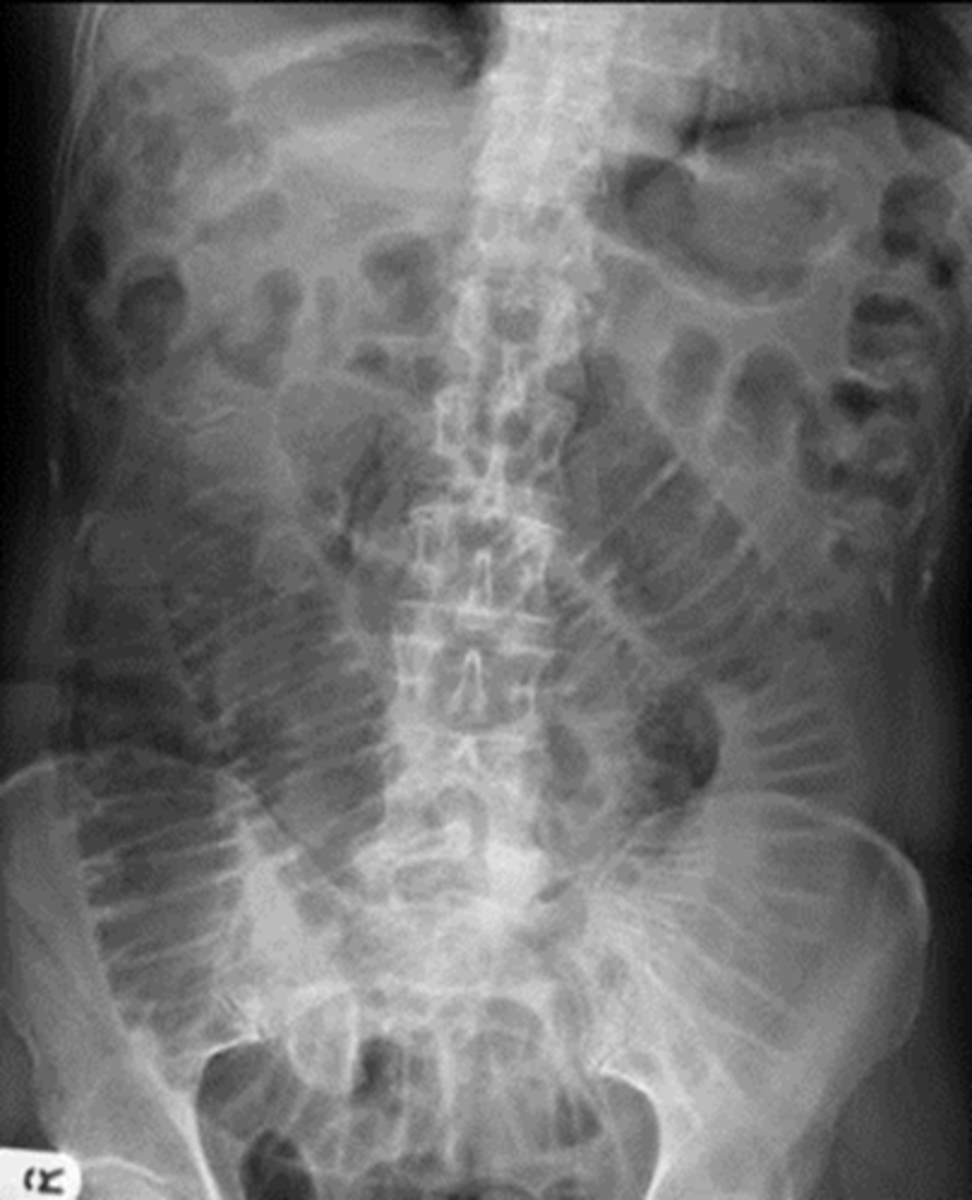

Normal supine abdomen

SOLID BLACK ARROW: small amount of air in about two or three loops of nondilated small bowel

DOTTED BLACK ARROW: air in stomach, always will have.

SOLID WHITE ARROW: air in the rectosigmoid colon.

DOTTED WHITE ARROWS: psoas muscles outlined by fat.